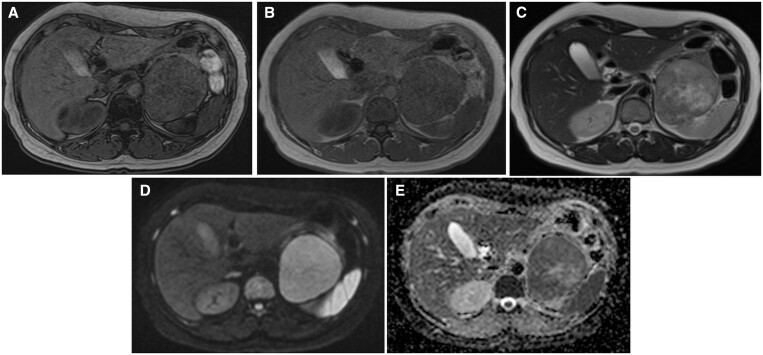

Oncocytoma is a tumour that predominantly occurs in the kidneys and salivary glands. Only approximately 200 cases have been reported to be of adrenal origin to date, and only a few reports about its radiological findings have been published so far. Herein, we present the CT and MRI findings of an adrenal oncocytoma observed in a patient suspected of having mitochondrial abnormalities, along with the pathological findings. The tumour was roughly classified into three areas: a hypercellular region, a region containing fibrous tissue, and an oedematous region. These corresponded to the restricted diffusion area on the apparent diffusion coefficient map, the gradually enhanced area at the secretory phase on contrast-enhanced CT scan, and the obvious hyperintensity on the T2-weighted image, respectively. We also discuss these findings in the context of previously reported radiological findings in the literature. Diagnosing adrenal oncocytoma through imaging is challenging, and it is crucial to consider the possibility of malignancy while making the differential diagnosis. Small-sized homogenous tumours may be hard to differentiate from lipid-poor adenomas, while larger inhomogeneous ones are hard to distinguish from adrenal cancer.

肿瘤细胞瘤是一种主要发生在肾脏和唾液腺的肿瘤。迄今为止,仅有约 200 例肾上腺来源的肿瘤被报道,而有关其放射学结果的报道也寥寥无几。在此,我们介绍了一名疑似线粒体异常患者肾上腺肿瘤的 CT 和 MRI 结果以及病理结果。肿瘤大致分为三个区域:高细胞区、含纤维组织区和水肿区。这些区域分别与表观扩散系数图上的扩散受限区、对比增强 CT 扫描中分泌期的逐渐增强区和 T2 加权图像上的明显高密度区相对应。我们还结合以前文献中报道的放射学结果对这些发现进行了讨论。通过影像学诊断肾上腺肿瘤细胞瘤具有挑战性,在进行鉴别诊断时考虑恶性肿瘤的可能性至关重要。体积较小的均质肿瘤可能很难与贫脂腺瘤相鉴别,而体积较大的不均质肿瘤则很难与肾上腺癌相鉴别。